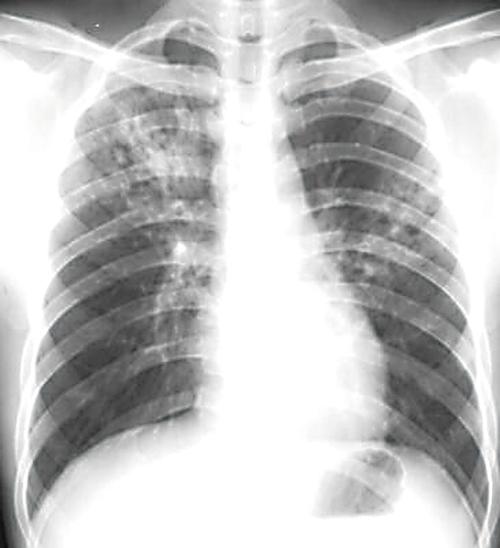

肺结核x光片

肺结核图片